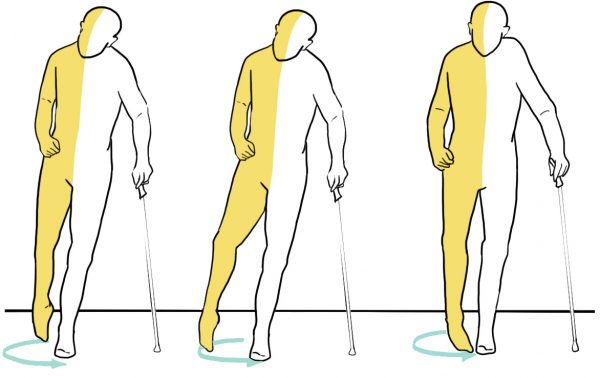

Opadająca stopa to schorzenie neurologiczne, uniemożliwiające uniesienie przodostopia. Powoduje ono, że palce ocierają o podłoże w trakcie chodu, dlatego pacjenci cierpiący na to schorzenie, często kompensują sobie dysfunkcję poprzez wysokie unoszenie kolana lub odwodzenie kończyny po łuku.

Orteza сharakteryzuje się lekkością i elastycznością, co osiągnięto poprzez zastosowanie najnowocześniejszych materiałów i technologii. Jest bardzo wytrzymała i na tyle dynamiczna i elastyczna, na ile to potrzebne. Jej systematyczne stosowanie pozwala na wytworzenie u pacjenta wzorca prawidłowego chodu, co zapobiegnie niepożądanym ruchom kompensacyjnym.

Orteza stopy AM-OSS-25 doskonale poprawia dynamikę chodu pacjenta, a także pasywnie i aktywnie koryguje inwersję stopy, gdyż poprzez układ specjalnych podciągów pobudza aktywność dźwigacza stopy oraz zwiększa zasięg kroku. Poprzez osiągnięcie prawidłowego wzorca chodu, aktywnie pracują mięśnie odpowiedzialne za chód tj. pośladkowe czy biodrowo-lędźwiowy. Orteza pozwala również na aktywną pracę pompy mięśniowej, która poprawia ukrwienie kończyn dolnych.